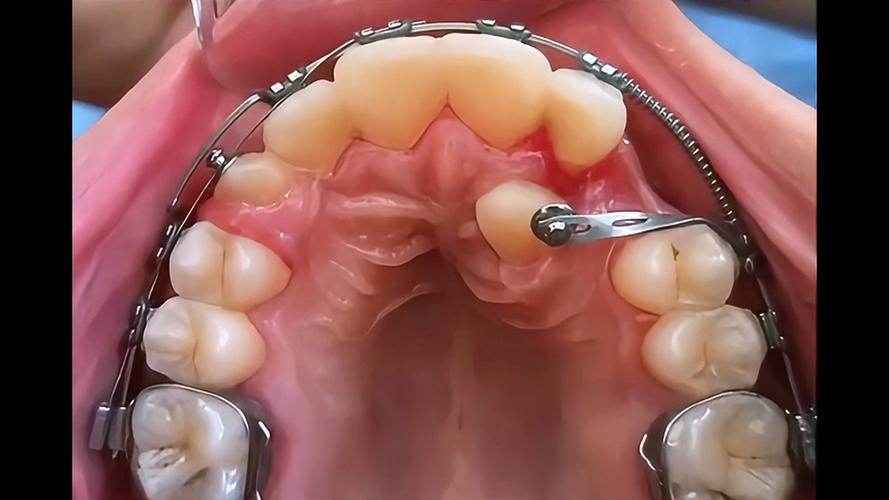

在北京进行隐形矫正,通常需经历系统化的流程,初诊阶段,医生会通过口腔检查、X光片(全景片、头颅侧位片)、CBCT(三维影像)等全面评估牙齿、颌骨、牙周状况,结合患者需求初步判断是否适合隐形矫正,若符合条件,下一步是数据采集:通过口内扫描仪获取牙齿三维数字模型,替代传统取模的 discomfort,精度更高且更高效,随后,医生利用专业软件进行方案设计,包括牙齿移动步骤、矫正周期、预期效果等,并与患者沟通确认,确保方案符合其预期,方案确定后,矫治器厂商会根据数字模型定制一系列透明牙套,通常每1-2周更换一副,通过持续、轻微的力引导牙齿移动至目标位置,整个矫正周期因人而异,一般需1-3年,期间需定期(每4-6周)复诊,医生会检查牙齿移动情况,调整方案或更换下一副牙套,矫正结束后,需佩戴保持器防止牙齿复发,保持器种类有透明压膜保持器、 Hawley保持器等,具体选择需遵医嘱。